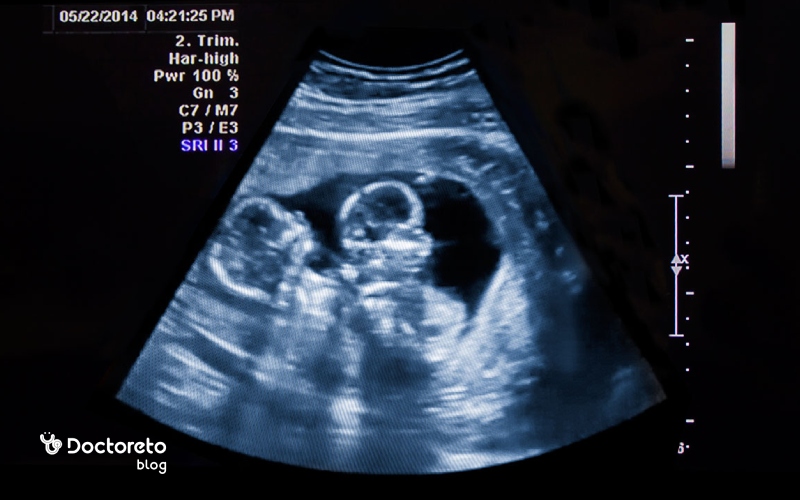

تشخیص بارداری دوقلو تنها با تست بارداری خانگی یا آزمایش خون امکانپذیر نیست، زیرا این تستها فقط وجود هورمون بارداری (β-hCG) را نشان میدهند و نمیتوانند تعداد جنین را مشخص کنند. در بارداری دوقلویی معمولاً سطح این هورمون بالاتر است و ممکن است تست خانگی زودتر یا پررنگتر مثبت شود، اما این موضوع قطعی نیست. آزمایش خون میتواند بارداری را زودتر از تست ادرار نشان دهد، اما باز هم قادر به تشخیص دوقلویی نیست. روش دقیق و مطمئن برای فهمیدن بارداری دوقلو، سونوگرافی در هفتههای اول بارداری است که وجود دو کیسه بارداری یا دو جنین را بهوضوح مشخص میکند.

بارداری دوقلو هفته به هفته معمولاً با تغییرات و علائمی شدیدتر از بارداری تکقلو همراه است. در هفتههای ابتدایی ممکن است نشانههایی مثل حساسیت سینهها، تهوع صبحگاهی، خستگی یا عقبافتادگی قاعدگی ظاهر شود. در سهماهه اول، تست بارداری خانگی میتواند نتیجه مثبت نشان دهد، اما تنها راه قطعی تشخیص دوقلویی، انجام سونوگرافی است. هرچند هفتههای نخست اغلب آرام میگذرند، اما با پیشرفت بارداری، فشار بیشتر بر بدن مادر باعث بروز علائم جدید و تجربههای متفاوت میشود. در ادامه به بررسی هفته های بارداری دوقلو و تغییرات هفته به هفته آن میپردازیم.